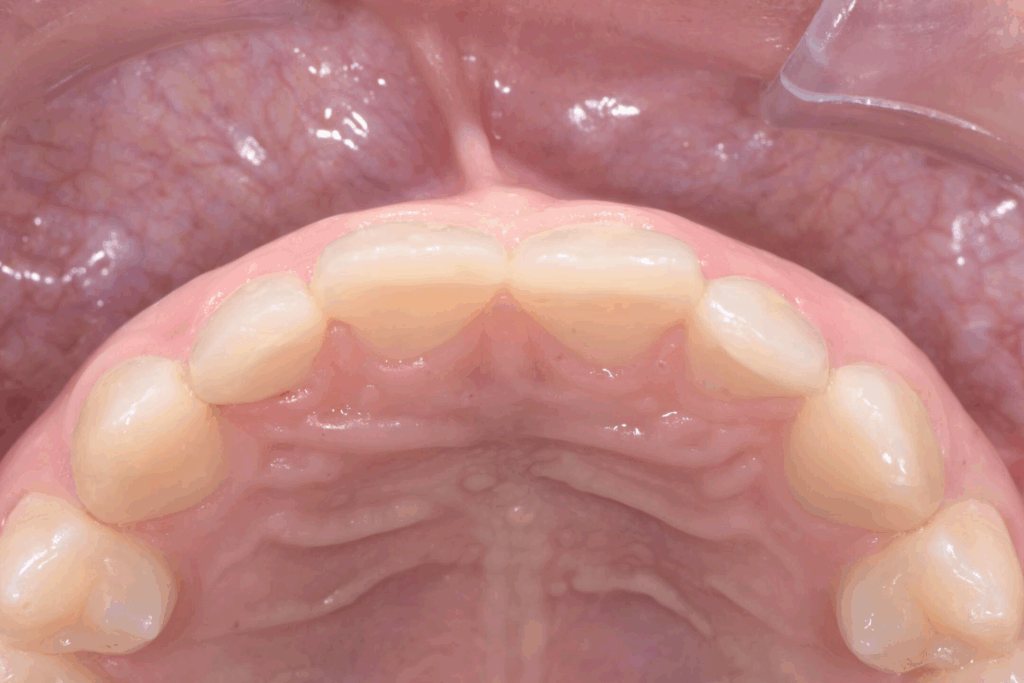

La prima fase del trattamento è stata un’analisi approfondita. Durante il check-up, abbiamo confermato la diagnosi di agenesia dei secondi molari permanenti inferiori, una condizione congenita che lascia spazi vuoti nell’arcata. Abbiamo inoltre rilevato che gli incisivi superiori erano di dimensioni ridotte rispetto al resto dei denti e che la paziente presentava un morso profondo, con gli incisivi superiori che coprivano eccessivamente quelli inferiori. Questa valutazione completa ci ha permesso di creare un piano di trattamento personalizzato e preciso, tenendo conto di tutte le problematiche presenti.

Una volta completata la fase ortodontica, siamo passati alla finalizzazione estetica degli incisivi superiori. Utilizzando la tecnica della ricostruzione in composito, abbiamo aumentato le dimensioni dei denti, migliorandone la forma e l’armonia con il resto del sorriso. Il composito, un materiale estetico e versatile, ci ha permesso di ottenere un risultato naturale e duraturo senza sacrificare la struttura dentale originale.

Risultato finale